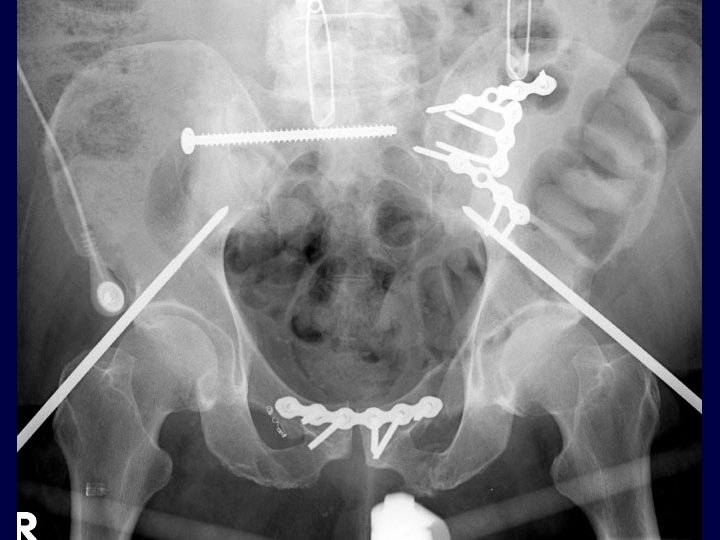

Immediate Percutaneous Fixation • From Chip Routt, MD